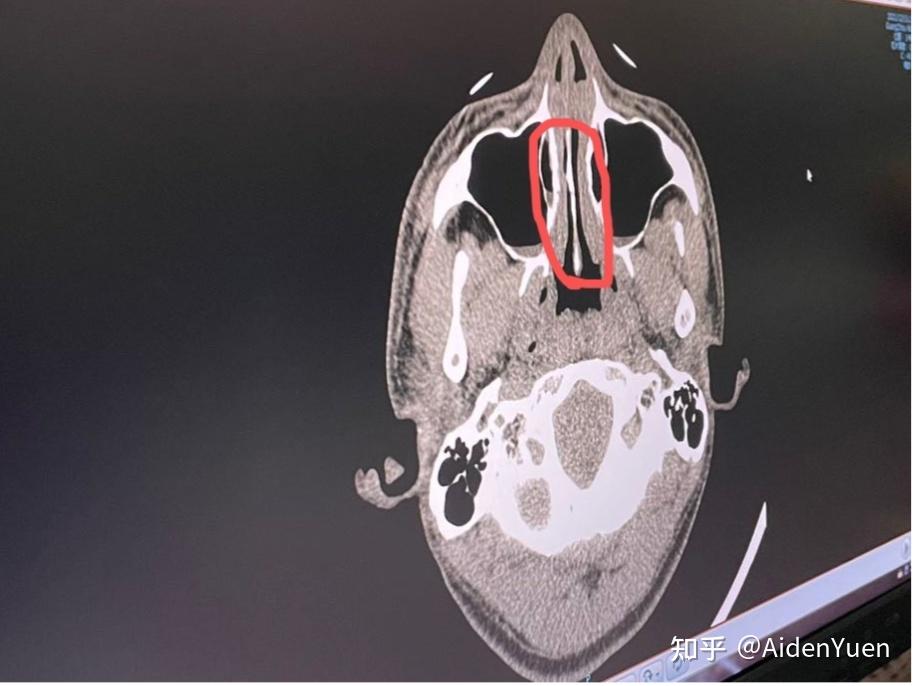

各位麻烦帮我看看这个ct片上我的这个鼻中隔偏曲算严重吗

图片尺寸1000x1333